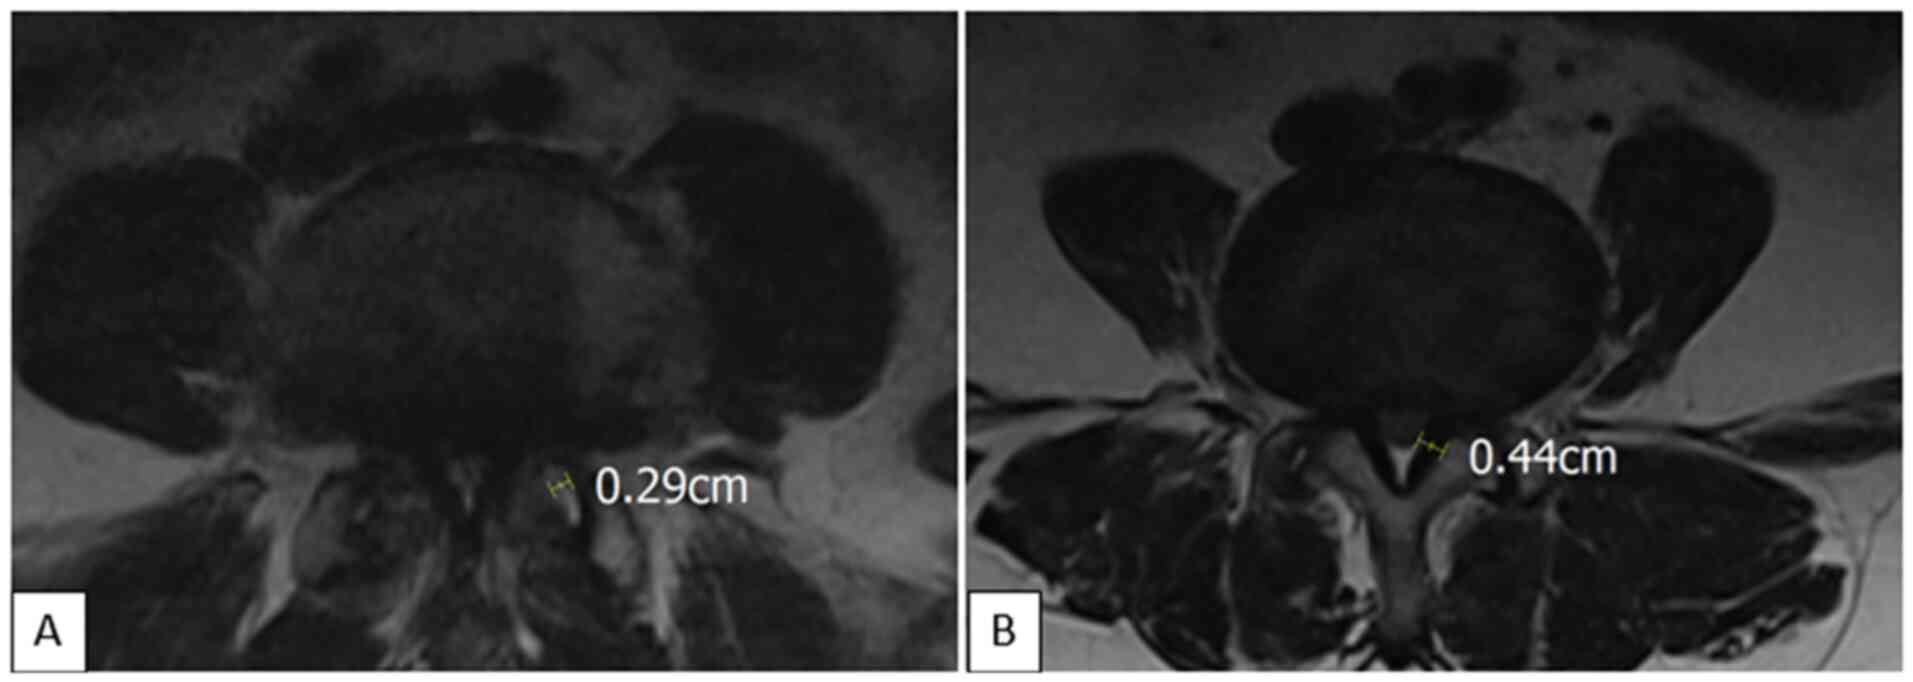

The disk height was determined by calculating the Farfan Index, as the sum of the anterior and posterior border heights divided by the disk width as measured on the sagittal plane of T2W images (Fig. 2) (16). Facet fluid was measured perpendicular to the joint at the site of greatest volume on axial T2W images (Fig. 3) (17,18). The ligamentum flavum was measured at the joint surface level on axial T2W images (Fig. 3) (19). Quantitative values for disk signal, including minimum, maximum, and mean signal values, were obtained by placing a region of interest (ROI) ellipse in the center of the intervertebral disk on sagittal T1W and T2W images (Fig. 2).

Figure 3

Facet fluid and ligamentum flavum thickness measurement. (A) Facet fluid thickness was measured as the length of a line perpendicular to the joint surface at the site of the thickest fluid on axial T2W. (B) The ligamentum flavum was measured at the joint surface level on axial T2W. T2W, T2-weighted image.